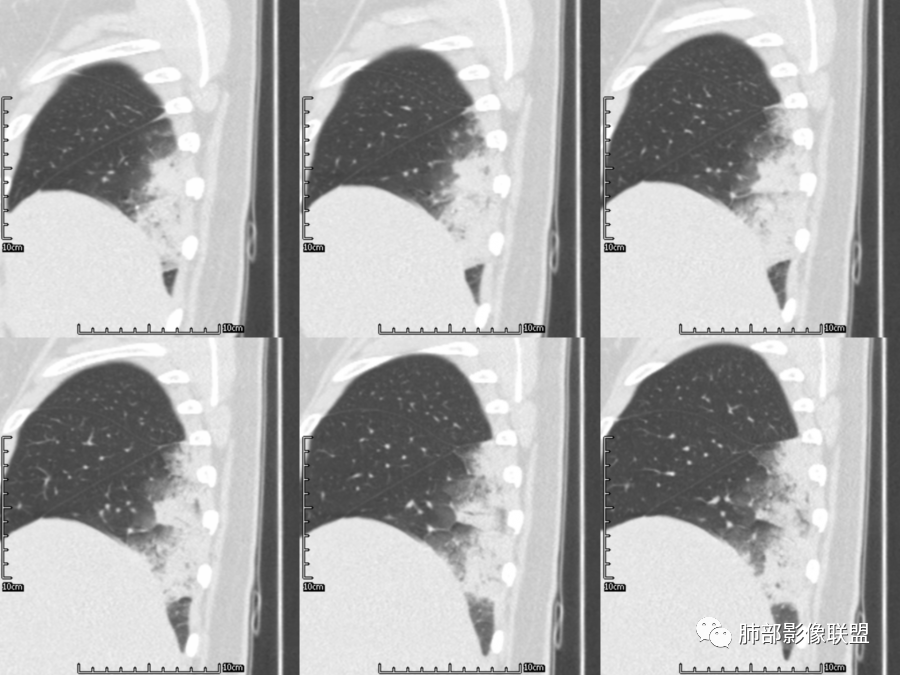

右肺胸膜下实变,病变跨多个叶生长,宽基底与胸膜相连,近端支气管穿行病灶内,并可见片状磨玻璃影,边界清,部分远端小支气管堵塞,支气管略有扩张,周围散发小结节,临床年轻女性,炎性指标高,发热六日,首先考虑感染性病变(肺链,奴卡,隐球,OP)鉴别淋巴瘤。

年轻女性,无明显诱因发热,体温略高,起病较急,有畏寒,右下肺紧贴胸膜下片状实变影,部分融合,外围有结节影,性质比较单一,类似于蘑菇兄弟,病灶周围伴有晕,支气管进入近端扩张远端堵塞,常规考虑感染,肺炎链球菌、隐球菌。

青年女性,发热咳嗽5天,炎症标志物升高。右肺下叶大片实变伴周围GGO,GGO内未见细网格,主体与胸膜平行,似多个病灶融合,实变区内见支气管部分进入,部分支气管受压狭窄,周围可见多发卫星病灶。支持炎性,考虑隐球感染,鉴别op。

年轻女性,急性起病,咳嗽,发热,黄痰,白细胞高,CRP基本正常,基础体健。CT提示右肺下叶实变,宽基底与胸膜相连,长轴平行于胸膜,可见支气管充气征,于病变中央截断,走形自然,胸膜下脂肪间隙可见,倾向于隐球菌,鉴别肺链,军团菌等。

年轻患者,右肺下叶大片状实变影,长轴与胸膜平行,内见含气支气管征,周围磨玻璃晕影。考虑感染性病变,隐球?

病灶长轴与胸膜平行,边缘有晕,病灶融合趋势,支气管进入,走行自如,考虑隐球菌肺炎。

年轻女性,急性发病,咳嗽咳痰五天,炎性指标升高,右肺下叶胸膜下大片实变影,周围见磨玻璃影,边界清晰,长轴与胸膜平行,呈融合趋势,支气管进入走行自然,远端截断,考虑炎性,隐球菌可能。

年轻女性,发热,急性发病,白细胞高,右肺下叶大片实变,长轴与胸膜平行,内见支气管走行,远端截断,周围有晕,晕边界清,考虑感染,隐球可能,鉴别淋巴瘤。

年轻女性,右肺下叶胸膜下多发实变、结节影,宽基底与胸膜相连,边缘模糊不清,实变内见支气管穿行,血象高,考虑感染性病变,大叶性肺炎?隐球?

青年女性,发热咳嗽急性起病,右肺下叶大片状实变密度影,长轴平行于胸膜,边缘模糊可见磨玻璃影及高密度结节影,实变内可见支气管穿行,直达病灶远端,考虑感染性病变,隐球菌可能大。

右肺胸膜下实变,病变跨多个叶生长,相互融合,宽基底与胸膜相连,支气管气象,并可见片状磨玻璃影,边界清,炎性指标高,发热六日,考虑感染病变,链球菌?腺病毒待排。

右肺下叶大片状实变影,长轴平行于胸膜,边缘模糊可见磨玻璃影,支气管进入,部分近端阻塞,考虑感染性病变,隐球菌,鉴别大叶性肺炎。

年轻女性,起病急,白细胞,C反高,存在感染。右下肺大片实变影,支气管充气征,长轴平行胸膜,似多个病灶融合,周围GGO,部分清,部分不清。考虑感染,隐球可能。

青年人,右肺多发团片状阴影,边缘模糊,周围可见磨玻璃影,内部有支气管空气征,考虑感染性病变,隐球菌感染可能。

右肺下叶大片状实变影,从外向内,长轴平行于胸膜,边缘模糊,可见磨玻璃影,支气管进入,远端部分阻塞,考虑感染性病变,隐球菌,鉴别淋巴瘤。

26岁,女性,发热、咳嗽5天。咳少量黄痰,起病急,病程短,白细胞及中性高,血沉及D-二聚体增高。胸部CT:右肺下叶大片实变,长轴沿胸膜分布,宽基底与胸膜接触,边界不清,周围GGO,部分团片影融合,病灶内可见支气管充气征,部分支气管进入病灶后阻塞。考虑:感染性病变,隐球菌?脓毒肺栓塞?鉴别:肺炎型肺Ca。

年轻女性,右肺下叶一大片实变影,似有多个结节影融合,周围有晕,内见支气管充气征,部分支气管进入后截断,病变近胸膜,长轴胸膜平行,考虑炎性,隐球菌首先考虑。

青年女性,影像表现右肺下叶胸膜下大片状实变影,近端见充气支气管征,边缘见片状磨玻璃影,下叶背段尚可见一结节。考虑感染性病变,隐球菌感染可能。

右下肺大片实变影,空气支气管征,边缘GGO,小叶间隔增厚,周围有蘑菇兄弟,基底宽,与胸膜平行,考虑隐球菌感染,鉴别肺炎型肺癌。

晨读:年轻女性,右肺胸膜下实变影,平行于胸膜,边缘磨玻璃影,内见支气管充气征,走形自然,略扩张。考虑感染性改变,隐球,肺链。2月发病,病毒性肺炎要考虑。鉴别淋巴瘤。

晨读:年轻女性,发热咳嗽5天。白细胞计数升高。右肺下叶大片状高密度影,边缘模糊,有实变 GGO,其内见支气管气相、无受压变细,无枯枝表现,其近端支气管无异常,右肺下叶背段见结节状影,定性考虑:炎症,隐球菌感染可能,炎症型肺癌不支持。

右下肺胸膜下大片状高密度影,其长轴与胸膜平行,病灶近端GGO模糊,部分支气管进入后阻断,支持感染性病变,考虑隐球菌

这个病变也不是一个起源中心,胸膜下,多发结节状、实变影。而大叶性肺炎多数由内-外大片状。所以是肺实质多发融合病变。单纯从影像上,还是比较符合隐球菌特点,胸膜下,多发、多中心,相互融合(兄弟齐心)。

隐球菌,胸膜下病灶,多个起源中心,最终还是融合在一起,侧向融合为主的。

隐球菌,侧向融合、外围胸膜下为主,也有累及叶段的、比较少。